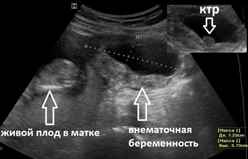

Видны ли признаки внематочной беременности на УЗИ?

УЗИ не всегда является информативным методом, так как на ранних сроках заметить плодное яйцо бывает невозможно и часто могут спутать сгустки крови или слизи в матке с маточной беременностью. Случалось наблюдать, что у женщины одновременно развивается две беременности, одна из которых маточная, которую и видит аппарат УЗИ, другая — внематочная. Если все же УЗИ тоже не подтверждает внематочную беременность, а подозрения на нее есть, то женщину могут положить в больницу для проведения соответствующей диагностики и лечения.